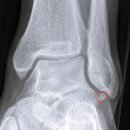

• 하부골 | [1주차] 발목 mbo 수술 & 비골하부골 제거 수술 후기

'23.12.18(월) 발목 인대재건술(mbo)과 비골하부골 제거 수술을 했다 2019년부터 올해까지ㅠ 1년에 한 번씩 넘어져서 반깁스를 했었고, 그때마다 어떤 병원을...오늘 ,, 아직 입원 중이고 ㅠ 2023 마지막 날에 갇혀 있는 게 우울해서 후기를 간단히 써봄 ,, ​ ​ '23.12.18(월) 수술 당일 ​ 입원 전날 밤 12시부터 금식...

• 하부골 | MBO 수술, 비골하부골 제거, 2개월 후 생활

걷기할때도 발바닥 전체가 땅을 닿을 수 있게 신경썼구요... ​ 헬스도 종종 하고 있지만 최대한 발목아껴서 쓸 수 있는 선에서 하고 있답니다. ​ 수술하기를 너무 잘했다.. 행복하자나... 특히나 MBO 수술, 비골하부골 제거에 대해서는 수술 후기가 많지 않아서 저도 정말~많이 찾아봤는데 모쪼록 도움이 되셨기를...